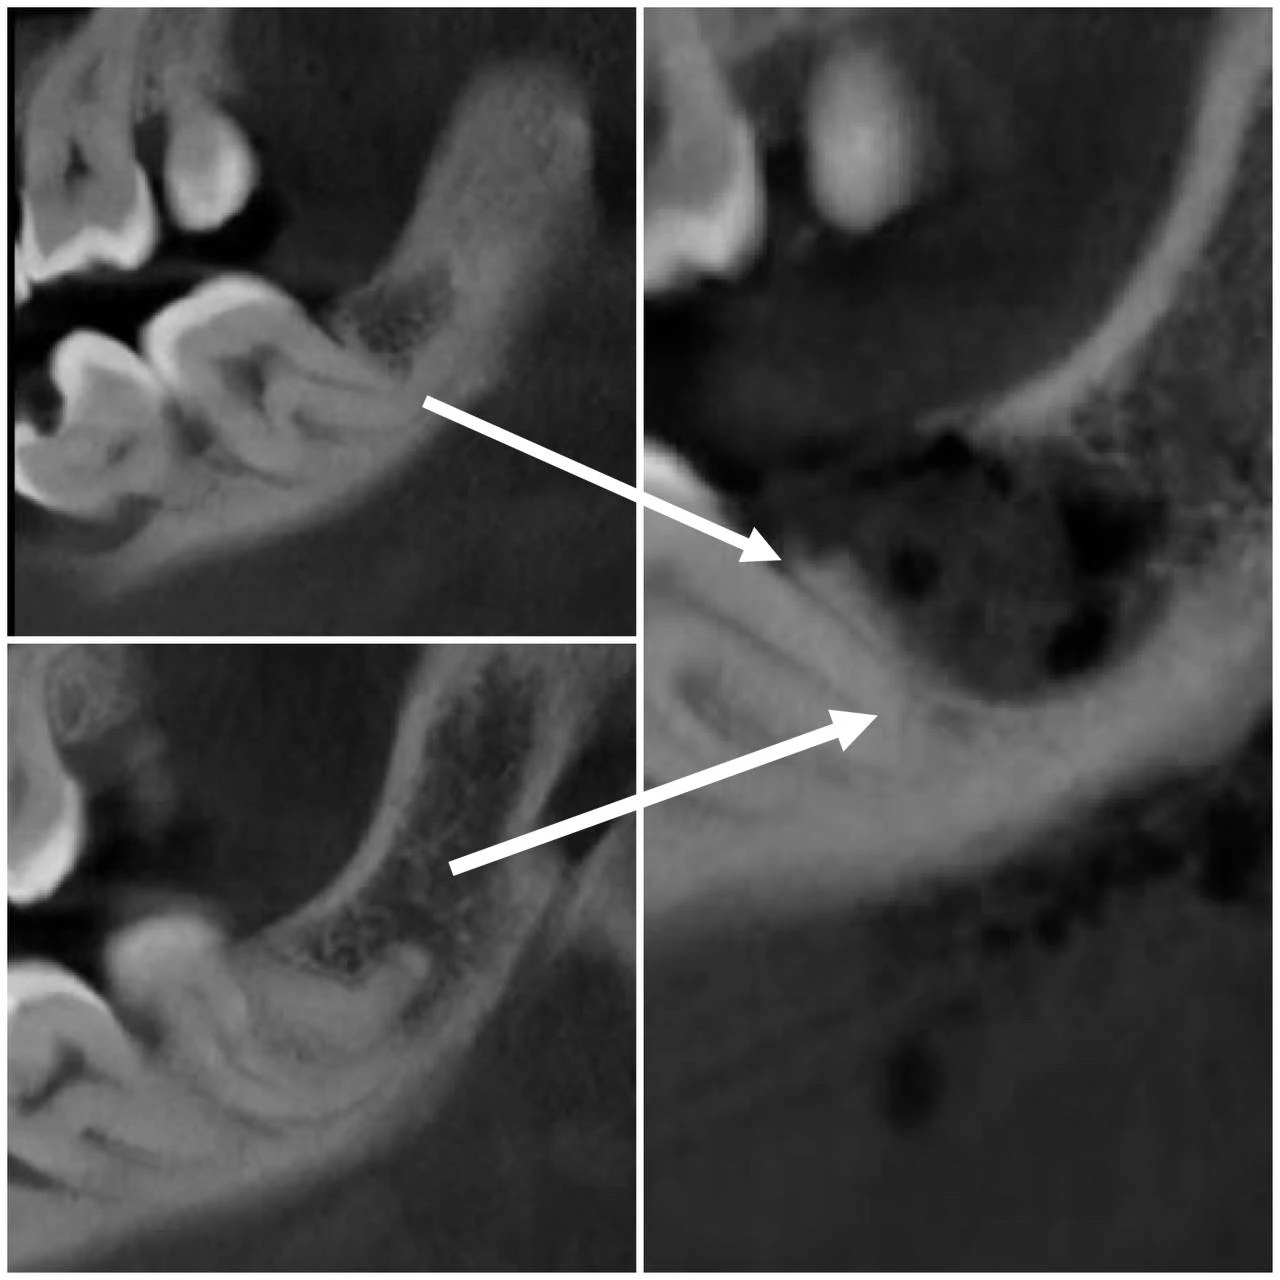

Видалення зуба 2.8,3.8